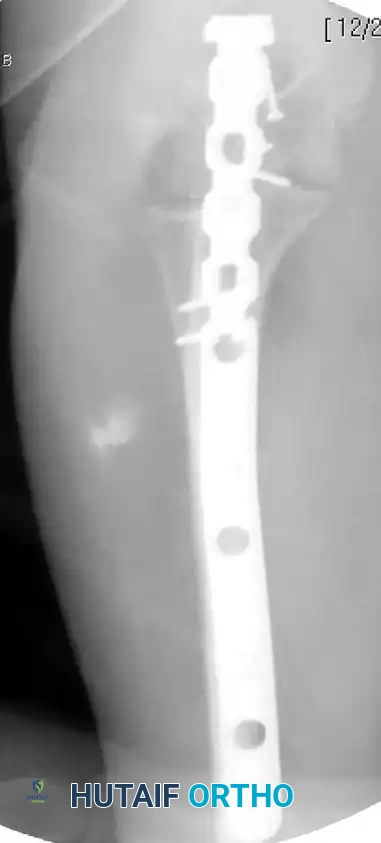

Complex Fracture-Dislocation of the Elbow (Pre-op AP):

Complex Fracture-Dislocation of the Elbow (Pre-op Lateral):

Fixation with Multiplanar Locking Intramedullary Nail (Post-op AP):

Fixation with Multiplanar Locking Intramedullary Nail (Post-op Lateral):

INTRAMEDULLARY NAILING FOR PROXIMAL ULNA FRACTURES

Recently, there has been a resurgence of interest in the use of intramedullary (IM) nails for the treatment of proximal ulna and olecranon fractures. The biomechanical advantage of IM nailing lies in its load-sharing capacity and minimal soft tissue disruption, which is highly advantageous in patients with compromised posterior skin envelopes.

More advanced, dedicated implants have since been developed. Nijs et al. reported excellent outcomes using an olecranon osteotomy nail (OleON, Synthes). Furthermore, Edwards et al. demonstrated the efficacy of a multiplanar locking intramedullary nail (OlecraNail, Mylad Orthopaedic Solutions) for the treatment of proximal olecranon fractures, including those presenting with complex, multi-directional instability patterns.